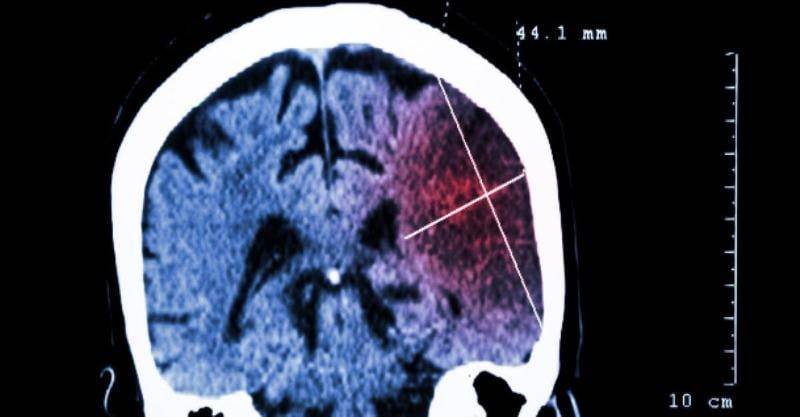

49歲的鄧先生,晨起後突然感到頭暈嘔吐,右側肢體也開始越來越乏力,到醫院的時候,右側肢體已經完全不能動了。

通過檢查,醫生髮現鄧先生所罹患的其實是急性腦梗,更糟糕的是,竟然還是大面積腦梗,鑒于病情危重,鄧先生被立刻送進重癥監護室治療,遺憾的是,雖然醫生盡全力搶救,但僅僅一周後,鄧先生還是不幸離世。

腦梗死又稱腦梗腦梗塞,是指大腦中的某個組織區域出現壞死情況。它是由向大腦供應血液和氧氣的動脈阻塞或狹窄所導致。由于血液供應受限,則會導致缺血性中風,如果血流在相對較短的時間內沒有及時恢復,就會出現梗塞